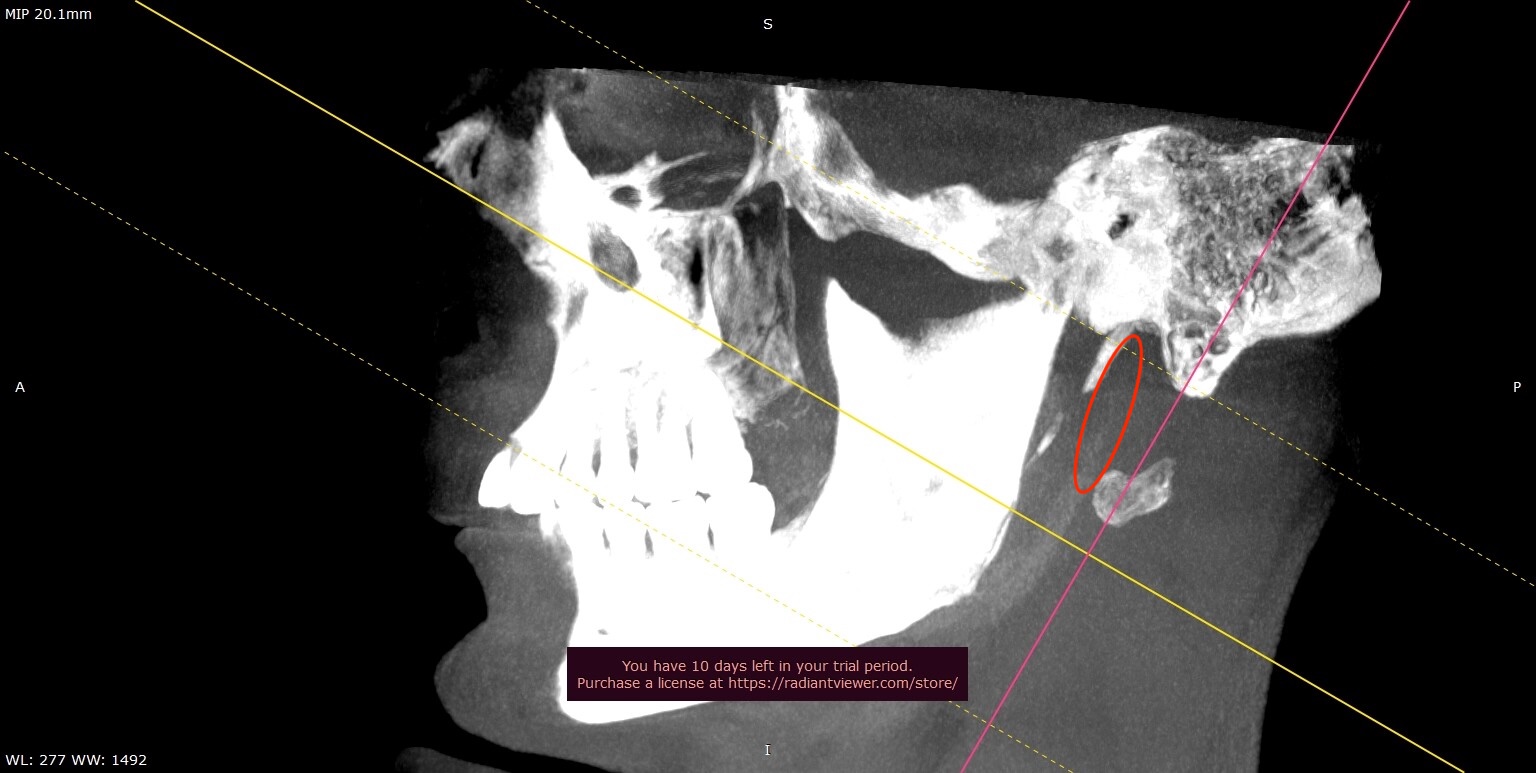

Hi @Isaiah_40_31 , I decided to spend some time looking at my MRI and MRA data wondering if there was anything left out of the report that might be of consequence. Combing through the MRI data is a little more of a challenge than a CBCT. However, looking at this set I was surprised to see something that looks distinctly like it’s under compression. I’m not sure if this is my jugular (right side) in the images below, but what ever it is it definitely looks like it’s getting pinched up against my C1. Am I reading this image correctly?

@wade - Good job sleuthing that out! It sure does look like your IJV is being squashed.

In retrospect, you can kind of see it here, too: